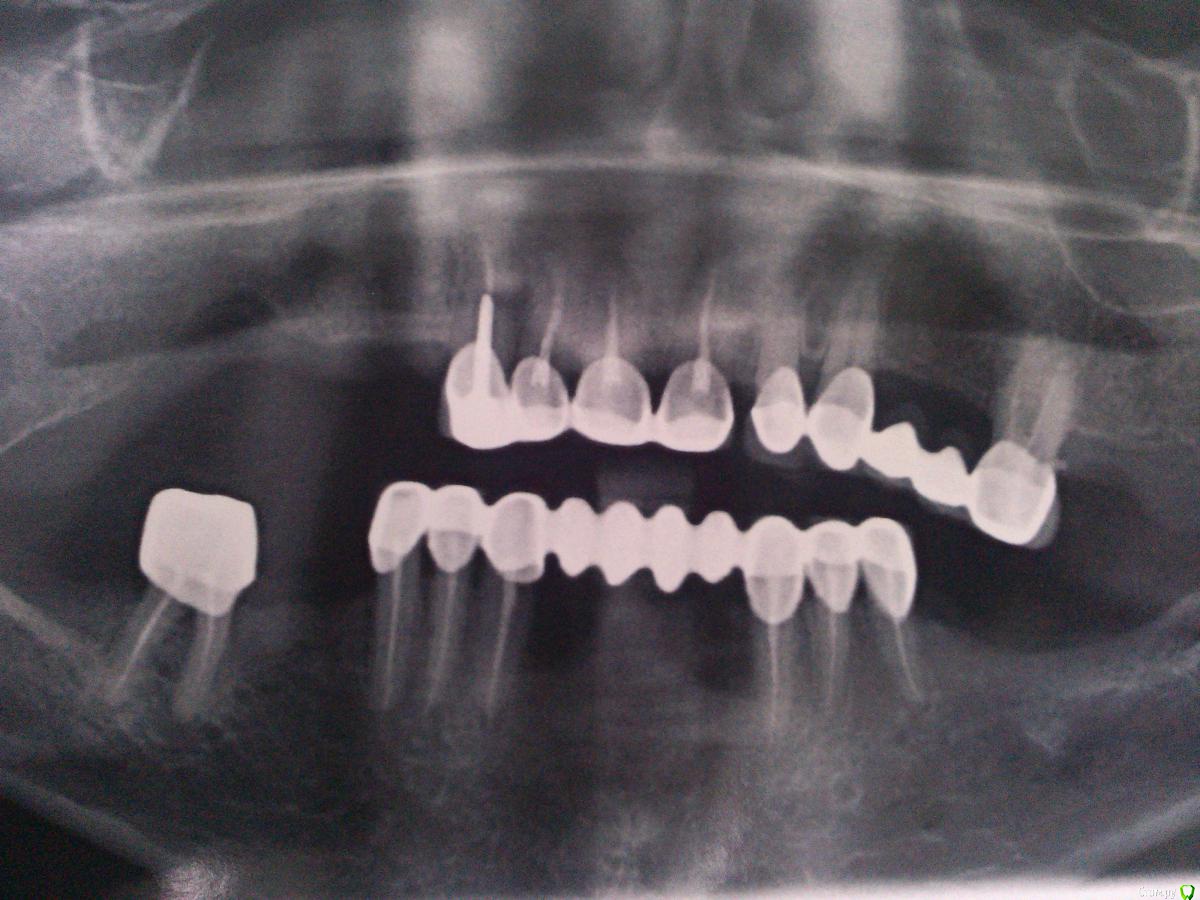

Невероятный Алк2 Опубликовано 31 марта, 2015 Поделиться Опубликовано 31 марта, 2015 Помогите спланировать план лечения. Пациентка протезировалась больше года назад в другом городе. Была у меня на консультации где то пол года назад, на тот момент были жалобы на то что зубы не смыкаются (фото тогда не делал). при осмотре была небольшая прогения и небольшая шель в области зубов 2.3 2.4 и 3.3 3.4. подкорректировал немного по прикусу по прикуссу и отпустил. вот она появилась снова утверждая что нижние зубы выдвигаются вперед. при осмотре то что на фото (за качество извините фоткал на телефон). пациентка хочет все переделать чтобы было красиво. у меня затруднения с выбором конструкции. если кто то что то посоветует, буду очень признателен. заранее спасибо. Ссылка на комментарий

Невероятный Алк2 Опубликовано 1 апреля, 2015 Автор Поделиться Опубликовано 1 апреля, 2015 Какого возраста девушка? Есть ли финансовые ограничения? Готова ли на полную переделку всего рта? Есть ли возможность имплантации или рассматривается только старое традиционное лечение? Есть хороший ортодонт рядом?1. Пациентка 54 года рождения.2. Вариант скорее больше бюджетный.3. По поводу переделки всего, от пациентки поступило предложение удалить весь низ и сделать полный съемный. Посоветовал ей не рубить с плеча.4. По поводу имплантации не разговаривали, но скорее нет чем да из финансовых соображений.5. Ортодонта не плохого найти можно если потребуется. Ссылка на комментарий

Doc Опубликовано 1 апреля, 2015 Поделиться Опубликовано 1 апреля, 2015 Понятно. Тогда для начала надо бы понять откуда такая прогения. По снимку не понять, то ли челюсть выдвинула, то ли запротезировали неправильно, то ли по жизни такая. Потому начать с определения правильного положения, сделать времянки или капу, перепрограммировать, потом протезировать. Внизу удалять все я бы не стал. Полный съемный это не подарок, тем более зубов хватает. Семерку да, пора вроде убрать, там бифуркации нет, а остальные под коронки и бюгель, либо просто съемный. Вверху та же история - смотреть что живет, что нет, потом коронки и съемный или бюгельный, в зависимости от финансовых возможностей пациентки. Из бюджетного без имплантации тут особо ничего не придумаешь. Ссылка на комментарий

Doc Опубликовано 1 апреля, 2015 Поделиться Опубликовано 1 апреля, 2015 Ну, если денег не считать, то справа вверху 3-4 импланта и слева вверху 2-3. Потом кругом коронки-мосты.Внизу два варианта вижу:1. Поставить два по центру и по два справа-слева, потом протезировать все коронками.2. Все снести и тогда еще два варианта: а). Все на четырех (делится еще на два варианта: х) балка и съемный, у) классический все на четырех); б). несъемный на шести имплантах. Ну, это кратко Ссылка на комментарий